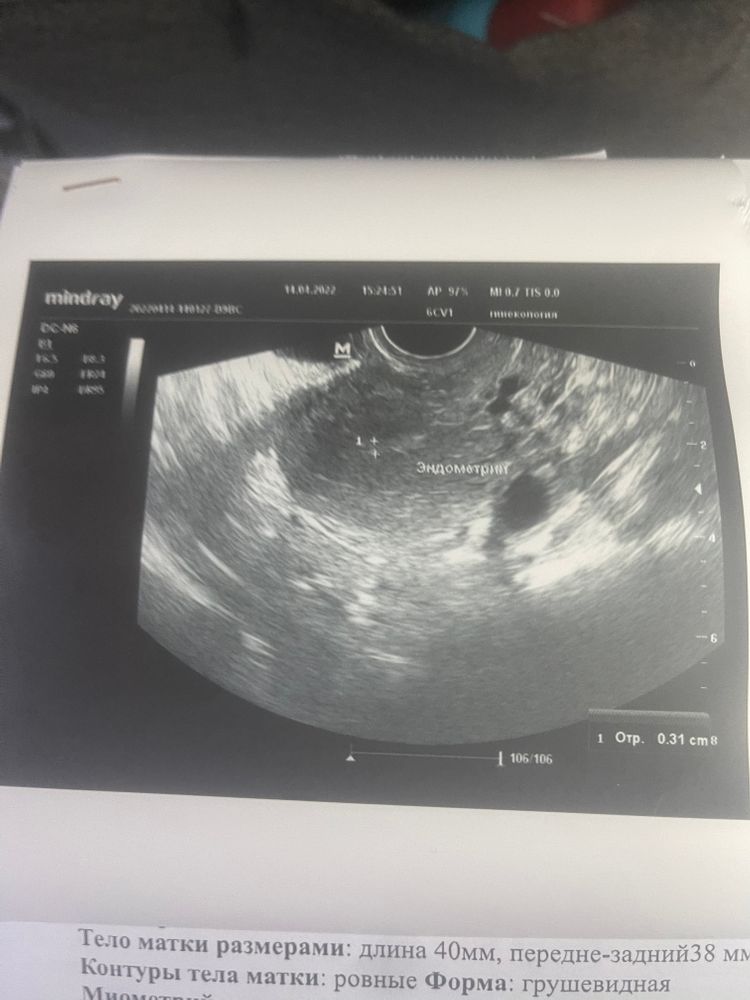

No Name в Зачатие 4 года Девочки, посмотрите тут есть плодное яйцо? Ждем дня Х (Признаки беременности / Тесты) Посмотрите еще 20 записей на эту тему Лучший ответ Ангелина Нет, в матке пусто 14.04.2022 Ответить Отменить Ответить Алекса Я бы сказала что нет, то что киста она не в эндометрии 14.04.2022 Ответить Признаки отсутствуют Может кто сталкивался с таким,какой был итог? Чаты Беременных Выберите чат: Январята-2026 Февралята-2026 Мартята-2026 Апрелята-2026 Майчата-2026 Июнята-2026 Июлята-2026 Августята-2026